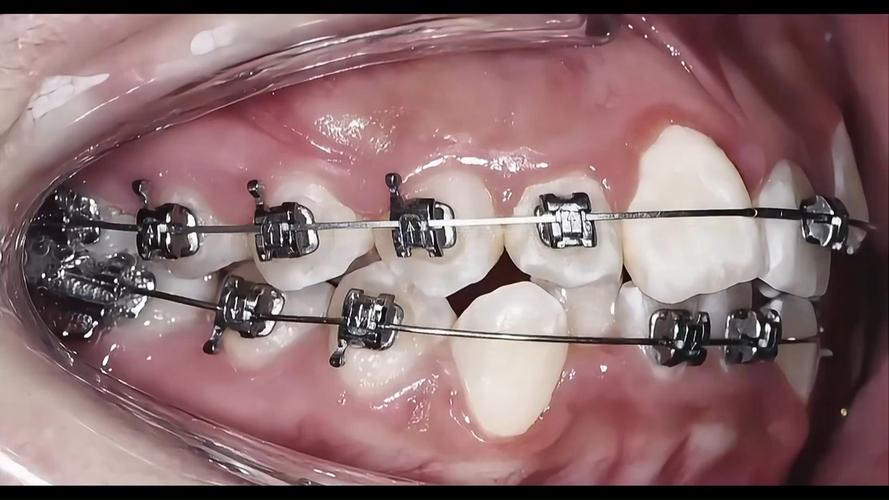

随着技术发展,牙齿矫正已从传统的“铁齿钢牙”演变为多种方式,每种方式的特点、价格、适合人群不同,需根据自身需求选择,以下为常见矫正方式的对比:

| 传统金属托槽 | 价格低、强度高、适用范围广(复杂畸形也可用) | 美观性差、易刮嘴、口腔异物感强 | 8000-15000 | 预算有限、牙齿畸形复杂者 | 1-2个月一次 |